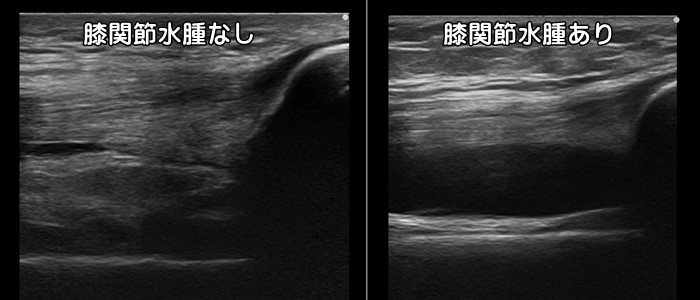

膝関節水腫

膝を曲げるとお皿の周辺が痛い場合は関節の袋(関節包)に水が溜まっている可能性があります。

膝を曲げると袋の中の水は移動するため、膝の裏側や外側など痛みの場所は変化します。